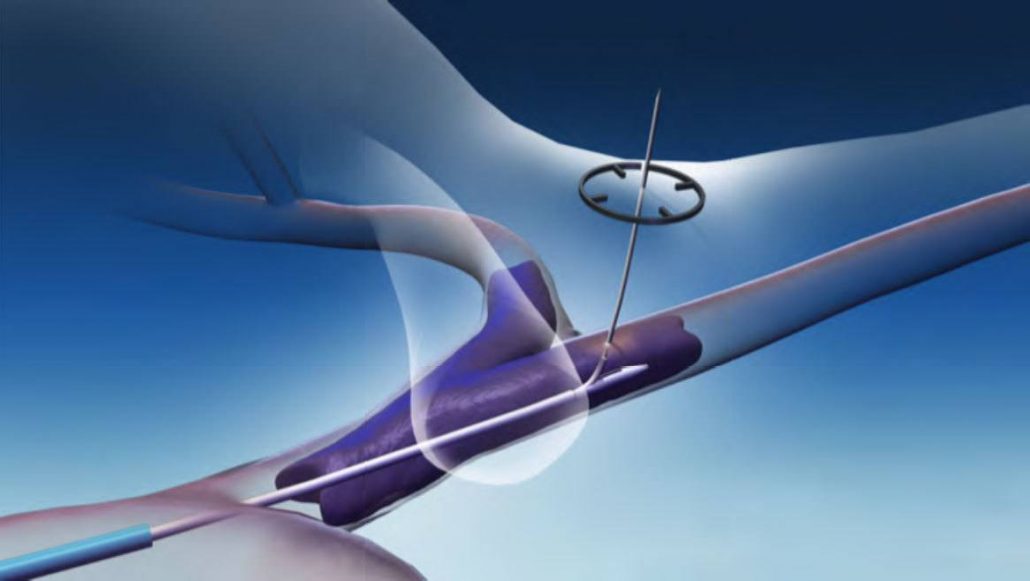

BENIGN PROSTATIC HYPERPLASIA (BPH)

Benign prostatic hyperplasia, or BPH, is the enlargement of the prostate gland and affects only men. It becomes more common as men get older. Up to 90% of men over the age of 80 have BPH. Although BPH is noncancerous, it can cause bothersome lower urinary tract symptoms.

Explore the products we offer to support prostatic artery embolization (PAE), a minimally invasive option to treat BPH.

MERIT PRODUCTS